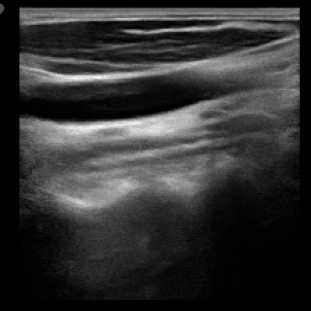

We propose a novel approach that adapts hierarchical vision foundation models for real-time ultrasound image segmentation. Existing ultrasound segmentation methods often struggle with adaptability to new tasks, relying on costly manual annotations, while real-time approaches generally fail to match state-of-the-art performance. To overcome these limitations, we introduce an adaptive framework that leverages the vision foundation model Hiera to extract multi-scale features, interleaved with DINOv2 representations to enhance visual expressiveness. These enriched features are then decoded to produce precise and robust segmentation. We conduct extensive evaluations on six public datasets and one in-house dataset, covering both cardiac and thyroid ultrasound segmentation. Experiments show that our approach outperforms state-of-the-art methods across multiple datasets and excels with limited supervision, surpassing nnUNet by over 20\% on average in the 1\% and 10\% data settings. Our method achieves $\sim$77 FPS inference speed with TensorRT on a single GPU, enabling real-time clinical applications.